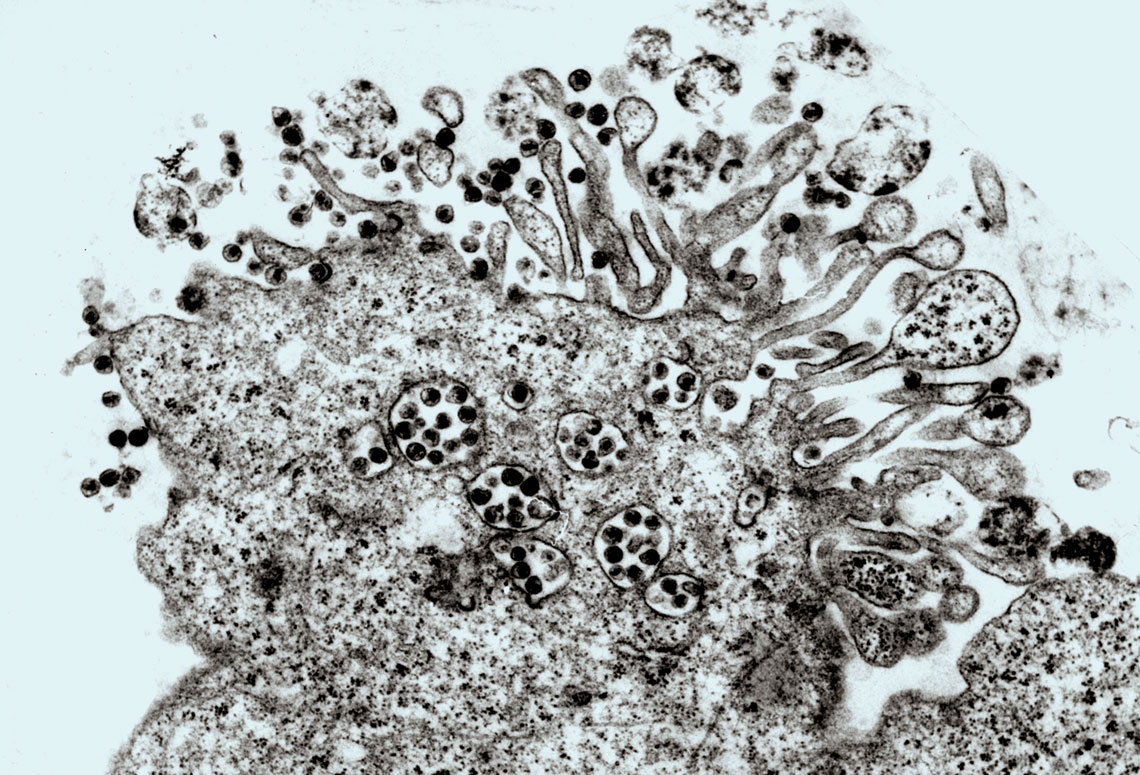

Registro de microscopia durante o isolamento inédito do HIV no Brasil, em 1987. Imagem: Monika Barth/IOC